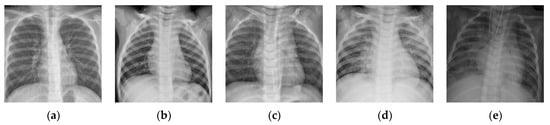

Figure 14.

Examples of the osteosarcoma histology images. (a) Non-tumor; (b,c) necrotic tumor; (d,e) viable tumor.

To further verify the applicability of the BSTriplet loss to other medical image modalities, additional experiments have been done on an osteosarcoma histology image dataset [48,49,50], which can be accessed from the cancer imaging archive (TCIA) [51]. There are three kinds of images in the osteosarcoma histology image dataset, as shown in Figure 14. Compared with the above involved images, the histology images are colored images, and their backgrounds are simpler than those of the skin rash images. This dataset is a small sample dataset and its construction is listed in Table 9. The augmentation for this dataset is the same as that for the rash images. We have clustered each kind of images into two groups for CE+BST loss according to the proposed data mining strategy. Using the accuracy , average sensitivity , average specificity and AUC as metrics, we have tested MobileNet-V3-Small trained with several different loss functions. The results are provided in Table 10 and Figure 15.